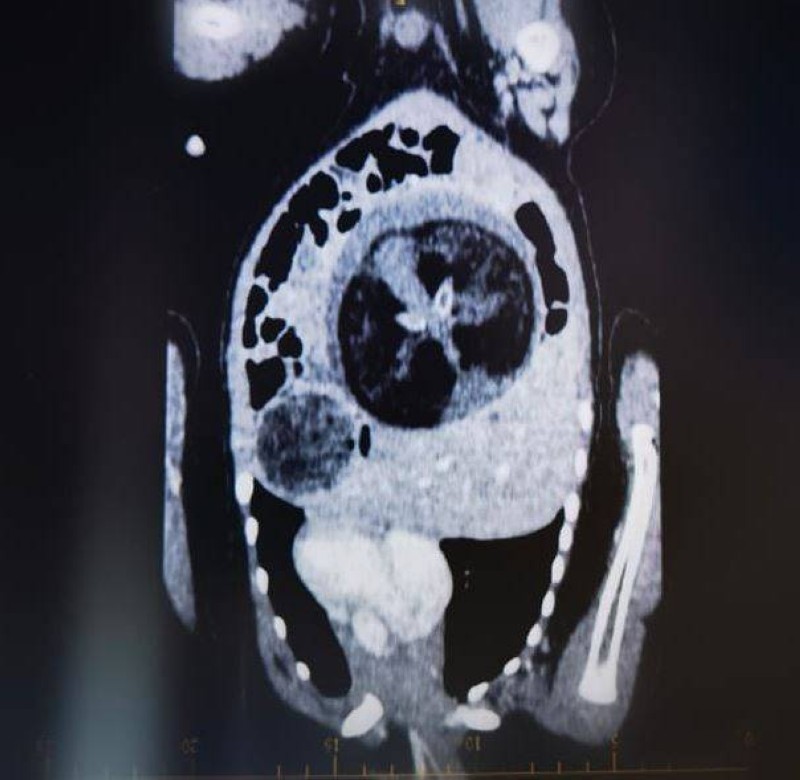

في حالة طبية نادرة، استأصل جراحو الأطفال بالمستشفى السلطاني بالعاصمة العمانية مسقط، جنينا من داخل بطن طفل ولد قبل 8 أشهر، وحين لوحظ انتفاخ بطنه بشكل غير طبيعي، كشفت الفحوصات أنه يحمل جنيناً مذ كان في رحم أمه. ووفق وكالة الأنباء العمانية (الأحد) وصف قائد الفريق الطبي رئيس قسم الجراحة الدكتور محمد الساجواني العملية الجراحية بالنادرة، كونها تتم في ظروف استثنائية. وقال: «بعد 3 أيام من الاستئصال تحققنا من الفحوصات والمؤشرات التي أثبتت نجاح هذه العملية النوعية. وتعرف هذه الظاهرة الطبية النادرة بـFetus in Feto، وتحدث بنسبة 1 بين كل 500 ألف حالة ولادة حية على مستوى العالم».